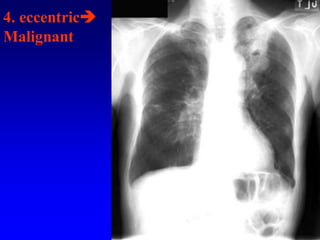

4. eccentric

Malignant